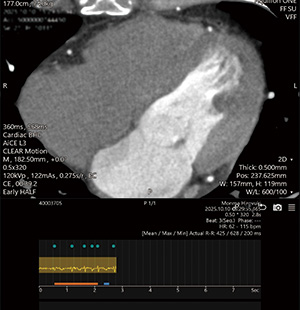

セグメント再構成

b

1ビートによるハーフ再構成

c

CLEAR Motionを使用

図2 心房細動

アブレーション術前肺静脈造影CT。心拍コントロールせず、複数ビート撮影。セグメント再構成(a)ではモーションアーチファクトが目立つが、1ビートによるハーフ再構成(b)にCLEAR Motionを使用することで、モーションアーチファクトの少ない画像が取得できた(c)。左房の評価目的であったが冠動脈の評価も可能となった。